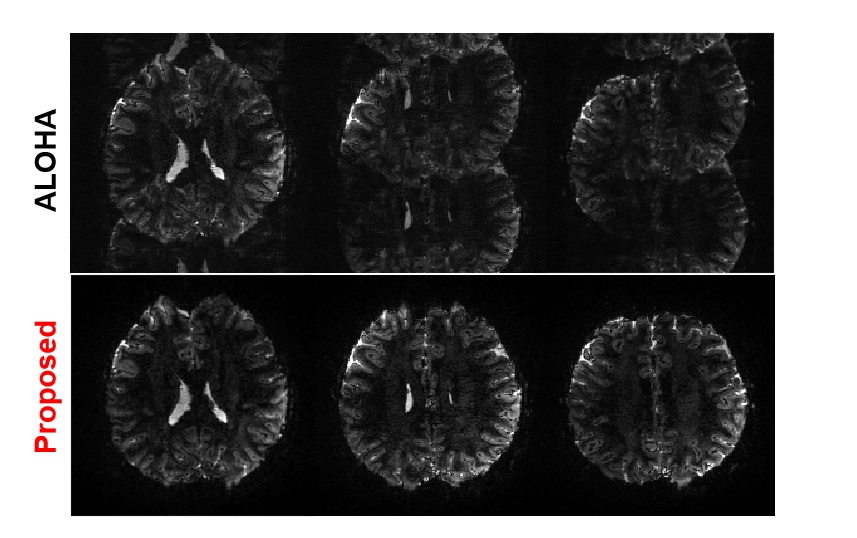

Recall that we used the ALOHA-based ghost correction images as label. However, as will be shown later, for high-field MRI, the ALOHA-based correction algorithm often fail to remove the ghost artifacts in some frames. Therefore, we visually inspected ALOHA-based ghost correction results, chose the ones with ghost corrected -space data, and use them as labels. Interestingly, as will be shown later, our trained neural network then successfully corrects the ghost artifacts even from the cases where ALOHA fails. Also, to make a robust neural network which can correct non-linear phase error, we additionally used simulated input data with non-linear phase error. The ratio of the original ghost input to the non-linear phase error simulation input was 50:50.

Recall that 7T EPI data is quite sensitive to the local field inhomogeneity, and the phase change is also large and nonlinear [16]. Therefore, the reference-based method which obtains a pre-scan from MR is often not able to perform the phase correction. Unlike the 3T EPI data, we found that ALOHA is not robust for 7T EPI due to the larger local field inhomogeneity variations. One could increase the matrix pencil size for the Hankel matrix to improve the performance of ALOHA, but the associated memory and computational complexity increases are sometime not acceptable in real applications. Moreover, with bigger matrix pencil size, the algorithm became more sensitive to other hyperparameters. Thus, ghost correction using ALOHA on 7T MR shows many failure cases. Specifically, from 6,250 set of slices in our experiment, we could get the only 1,346 successful cases for ghost correction using the ALOHA. Thus, only 1,346 successful cases are used as label data for our neural network training. Fig. 9 shows representative failure cases from the test data by the ALOHA-based ghost correction for 7T data. Interestingly, as shown in Fig. 9, even for the failure cases by ALOHA, the proposed method successfully corrected the ghost artifacts. In fact, among all data we used, no failure cases were observed using the proposed -space deep learning approach for ghost correction. This shows that the proposed algorithm is very robust even under large local field inhomogeneity changes. Even in the cases where ALOHA was successful, the proposed method mostly outperforms ALOHA as shown in fig. 5 and fig. 6. Given that CNN is closely related to ALOHA, this phenomenon may appear mysterious. However, in CNN approaches, the resulting receptive field size from the U-Net covers all image, resulting in significantly large matrix pencil size. Moreover, as discussed before in detail, despite the use of the same filter coefficients, the number of distinct basis representation increases exponentially with the depth and width thank to the combinatorial nature of ReLU [29]. This is in contrast to the data specific representation learning from Hankel matrix decomposition, which results in single linear representation. Therefore, the CNN approaches have significant advantages in terms of generalization capability and expressivity, which is not observed in the low-rank Hankel matrix decomposition.